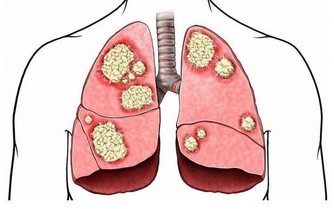

免疫系統紊亂

• 反復發生多發性口腔潰瘍,同時或前後伴有外生殖器潰瘍,皮膚出現痤瘡、毛囊炎,眼睛不適、視力下降,應考慮白塞氏病。

• 口腔潰瘍前後伴有脫髮,顏面部紫紅斑,關節疼痛等症狀時可能是紅斑狼瘡所致。

• 口腔潰瘍伴有持續發熱,頻繁感染應考慮血液系統疾病。